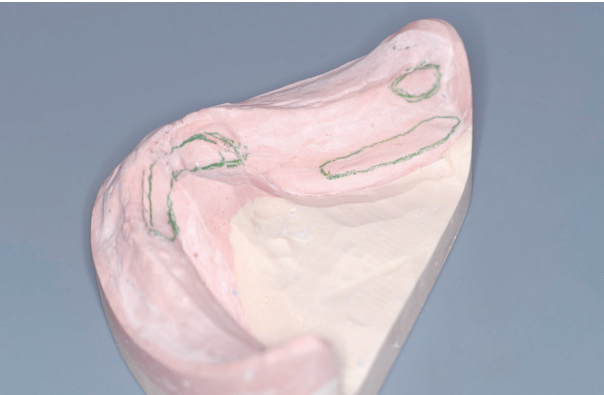

•Sublingual fold

Suction흡착과 folding 이중봉쇄

하악 틀니 유지력을 가장 약화시키는 부위가 이 부위이다.

혀는 개구 시 후상방으로 이동한다. 이때 틀니를 들뜨게 하는 힘이 작용한다.

이 부위 잇몸과 틀니 인상면 사이에서 형성되는 suction 흡착은 강하지 않다.

연마면에서 sublingual fold의 스펀지상의 부드러운 조직이 미약하지만 folding 이중봉쇄를 제공한다.

스펀지상의 부드러운 조직이 부족하면 틀니 연마면에서 folding 이중봉쇄가 형성되지 않아 개구 시에 유지력을 저하시킨다.

•Mylohyoid fossa

Mylohyoid ridge 후, 하방 공간은 유지력에 중요한 mechanical seal 기계적 봉쇄가 형성되는 공간이다.

이 부위는 설근부 측면이 틀니 구치부 설측 연마면을 압박하는 방법으로 틀니를 안정시킨다.

이 힘을 이용하려면 틀니 변연을 mylohyoid ridge 하방으로 2~3mm 연장해야 한다.

인상을 정확하게 채득하면 대부분 경우에 2~3mm 연장할 수 있는 공간을 확보할 수 있다.